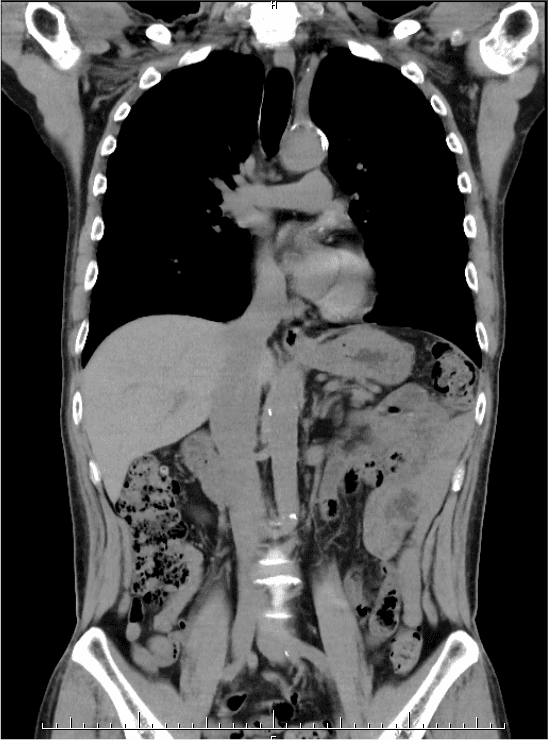

胸腹部CT + 体幹部筋肉・脂肪測定

胸腹部CTで肺や腹部臓器の病気、フレイルの早期発見をサポート

胸腹部CT検査では、肺や腹部臓器を高精度にチェックできます。早期の肺疾患や消化器系の病気(肝臓、膵臓、胆嚢、腎臓など)を発見することができ、早期治療のきっかけになります。

また体幹部の筋肉(脊柱起立筋、腸腰筋、腹筋、側筋)・脂肪の量を測定することで、フレイル(※)に早めに気づき、対策をとって防ぐ、あるいは遅らせることができます。

血管の石灰化の有無を観察することで、脳血管疾患や心疾患などのリスクを事前に察知することが可能です。 - 腹部臓器の異常を検出:

肝臓、膵臓、胆嚢、腎臓などの病気(腫瘍や炎症など)を見つけ出すことができます。 - 非侵襲的で簡単:

体幹部筋肉・脂肪測定に関して

体幹部の筋肉・脂肪量の測定は特殊なソフト(MVision body)を用いて、CT画像を元に測定しています。

※筋肉量の測定は脊柱起立筋、腸腰筋、腹筋、側筋の4種類